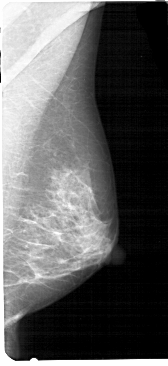

A_1203_1.LEFT_MLO

LEFT_MLO LINES 5341 PIXELS_PER_LINE 2416 BITS_PER_PIXEL 12 RESOLUTION 43.5 OVERLAY

FILE: A_1203_1.LEFT_MLO.OVERLAY

TOTAL_ABNORMALITIES 1

ABNORMALITY 1

LESION_TYPE MASS SHAPE ARCHITECTURAL_DISTORTION MARGINS SPICULATED

ASSESSMENT 4

SUBTLETY 2

PATHOLOGY MALIGNANT

TOTAL_OUTLINES 1